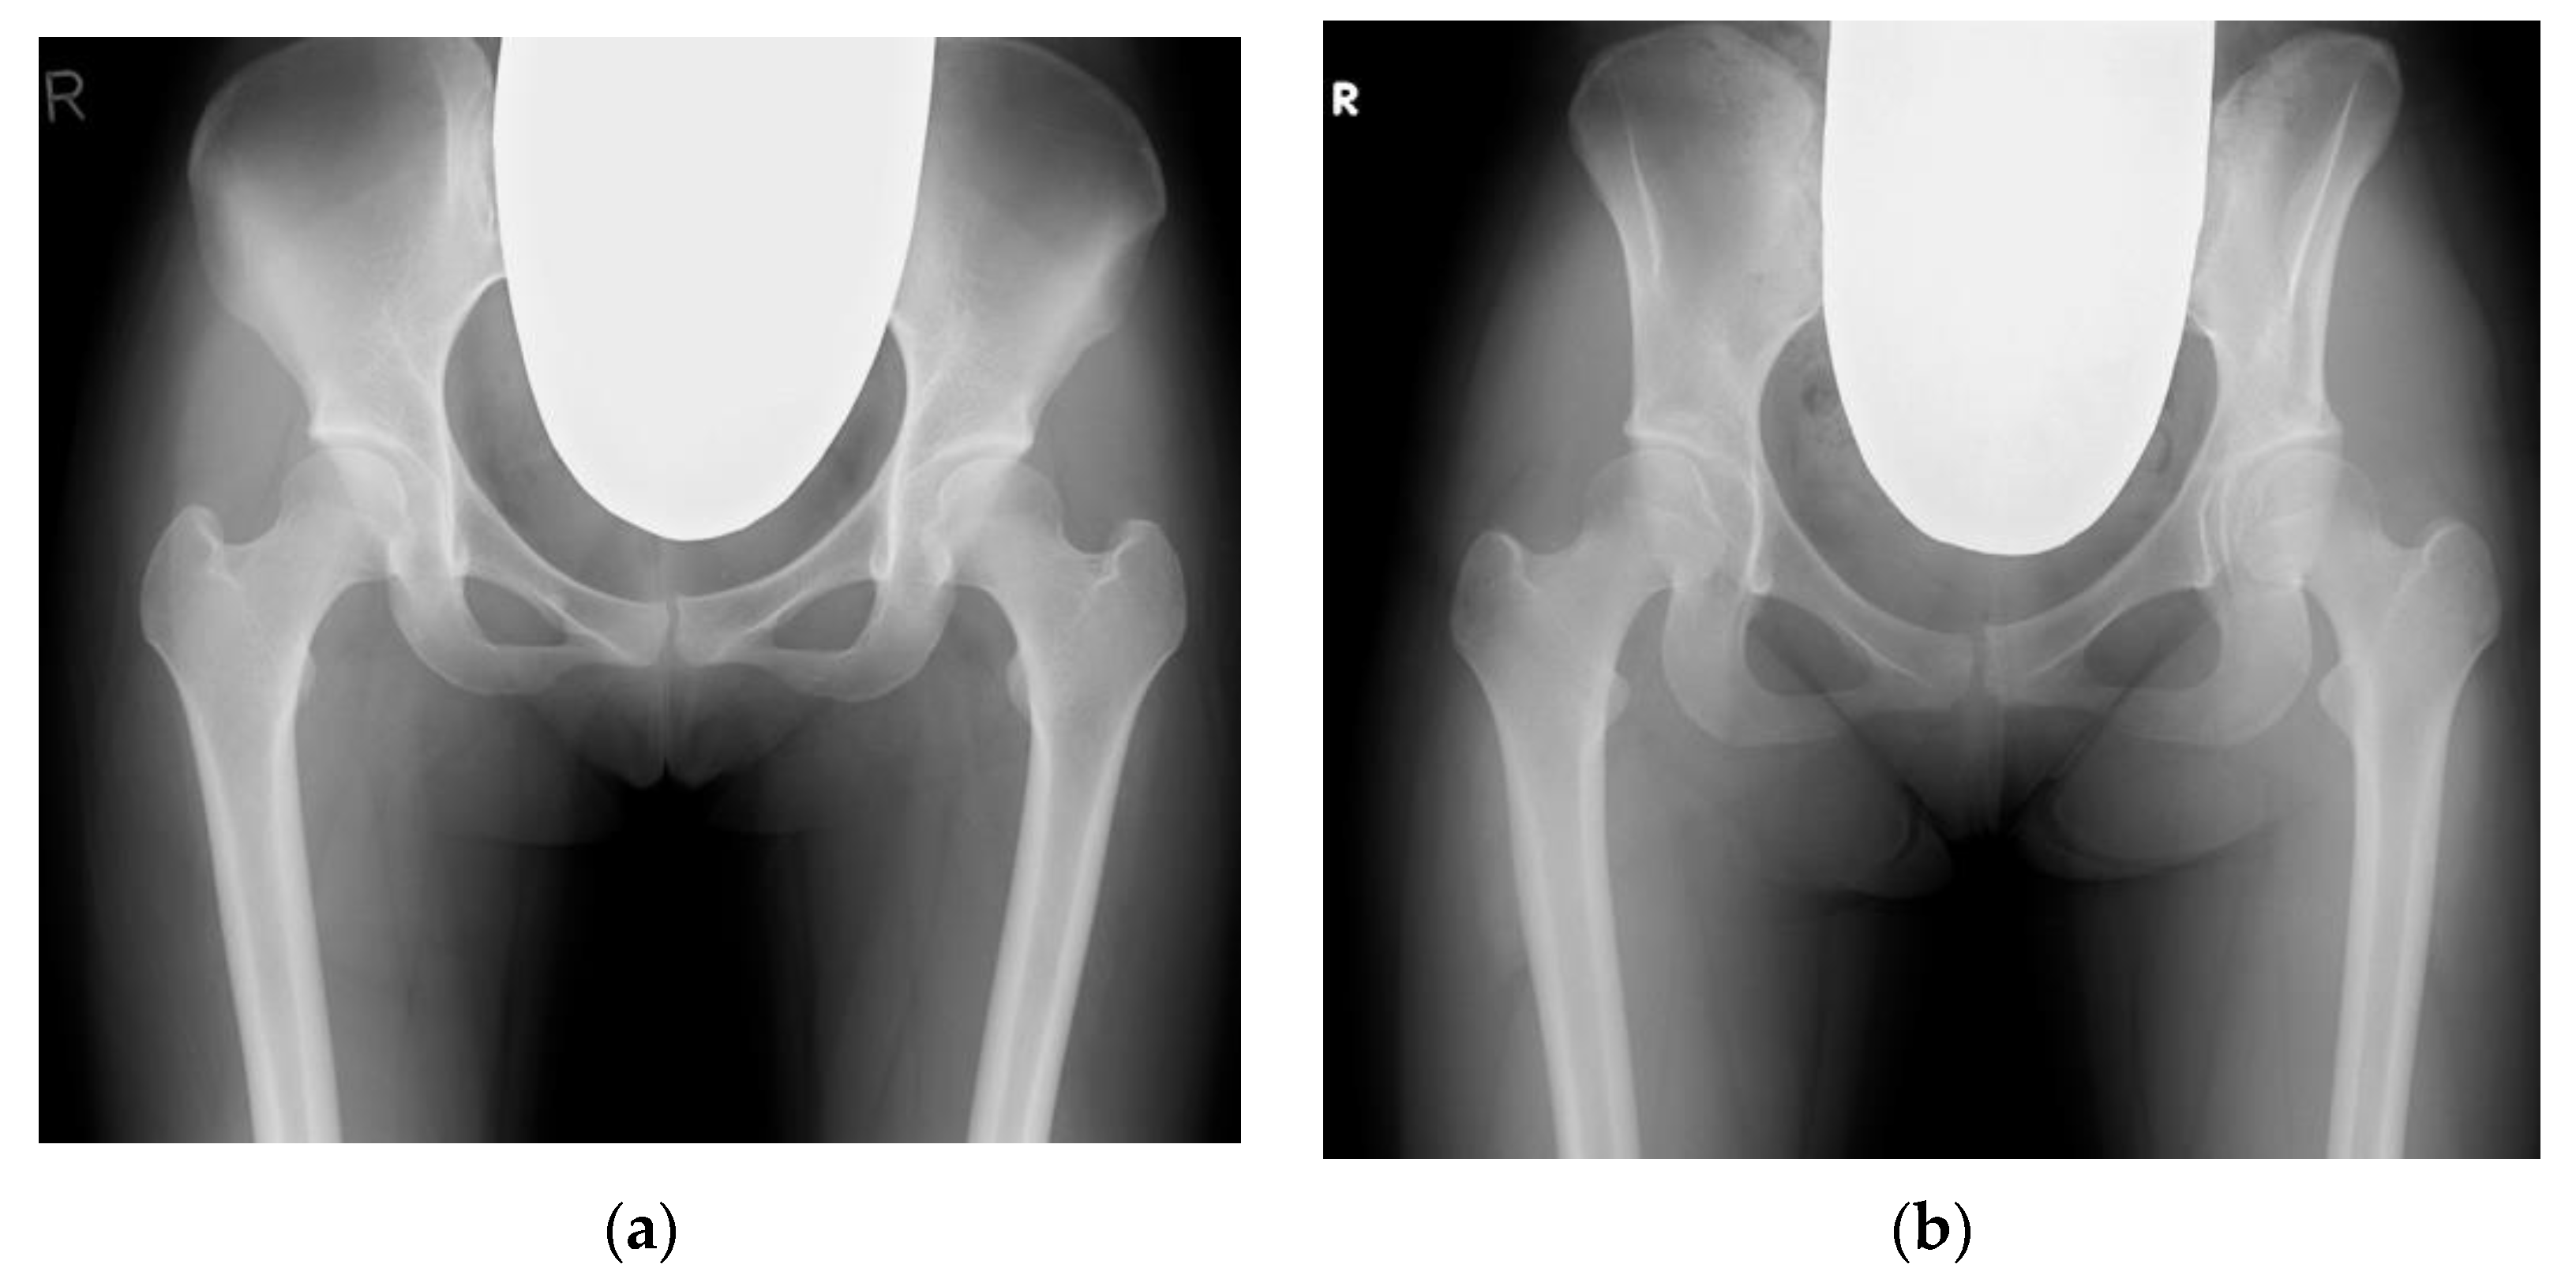

- Morimoto, T.; Kitajima, M.; Tsukamoto, M.; Yoshihara, T.; Sonohata, M.; Mawatari, M. Sagittal spino-pelvic alignment in rapidly destructive coxarthrosis. Eur. Spine J. 2018, 27, 475–481. [Google Scholar] [CrossRef]

- Onishi, E.; Ota, S.; Fujita, S.; Tsukamoto, Y.; Yamashita, S.; Hashimura, T.; Matsunaga, K.; Yasuda, T. Association between sagittal spinopelvic alignment and femoral head destruction in the early stage of rapidly destructive coxopathy. Bone Jt. Open 2022, 3, 77–84. [Google Scholar] [CrossRef]